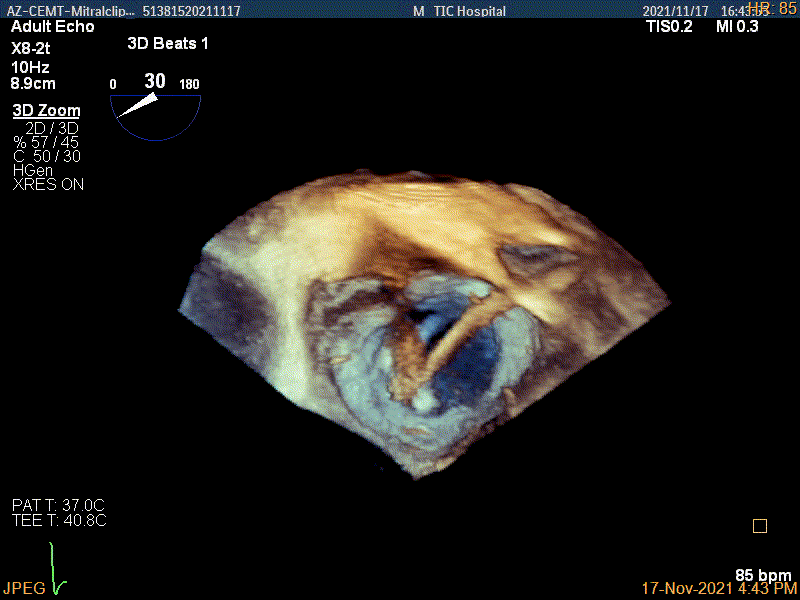

3D视图下进夹子并建立trajectory

3D视图打开夹子

Multivue视图下将夹子正对AC区并调节Rotate

3D证实夹子内侧残余脱垂(P1区)

3D视图下进第二个夹子并建立trajectory

将第二个夹子置于第一个夹子内侧尽量靠近,并调节Rotate呈尽量平行关系

3D视图两个夹子近似并排排列